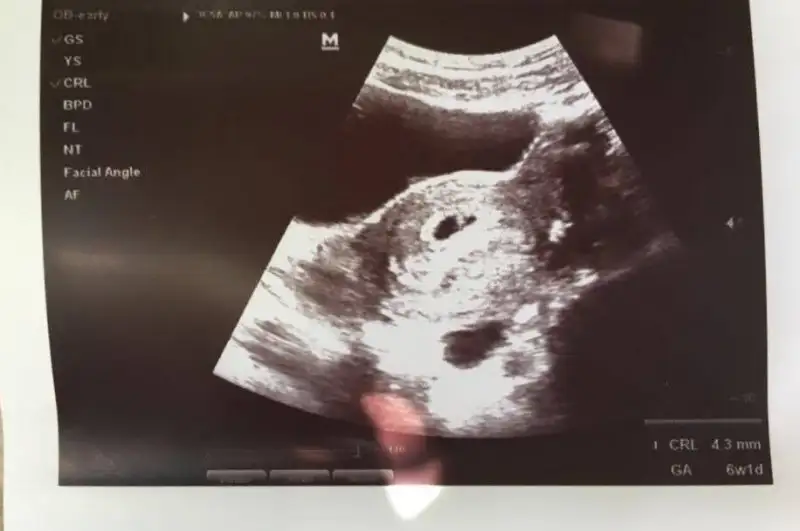

Kızlar merhaba benim bebişim için de cinsiyet tahmininde bulunabilir misiniz? Karından ultrason 6+1 ve 7+5 :)

• 6+1.webp

6+1.webp

13 KB · Görüntüleme: 217

• 7+5.webp

7+5.webp

14,1 KB · Görüntüleme: 249